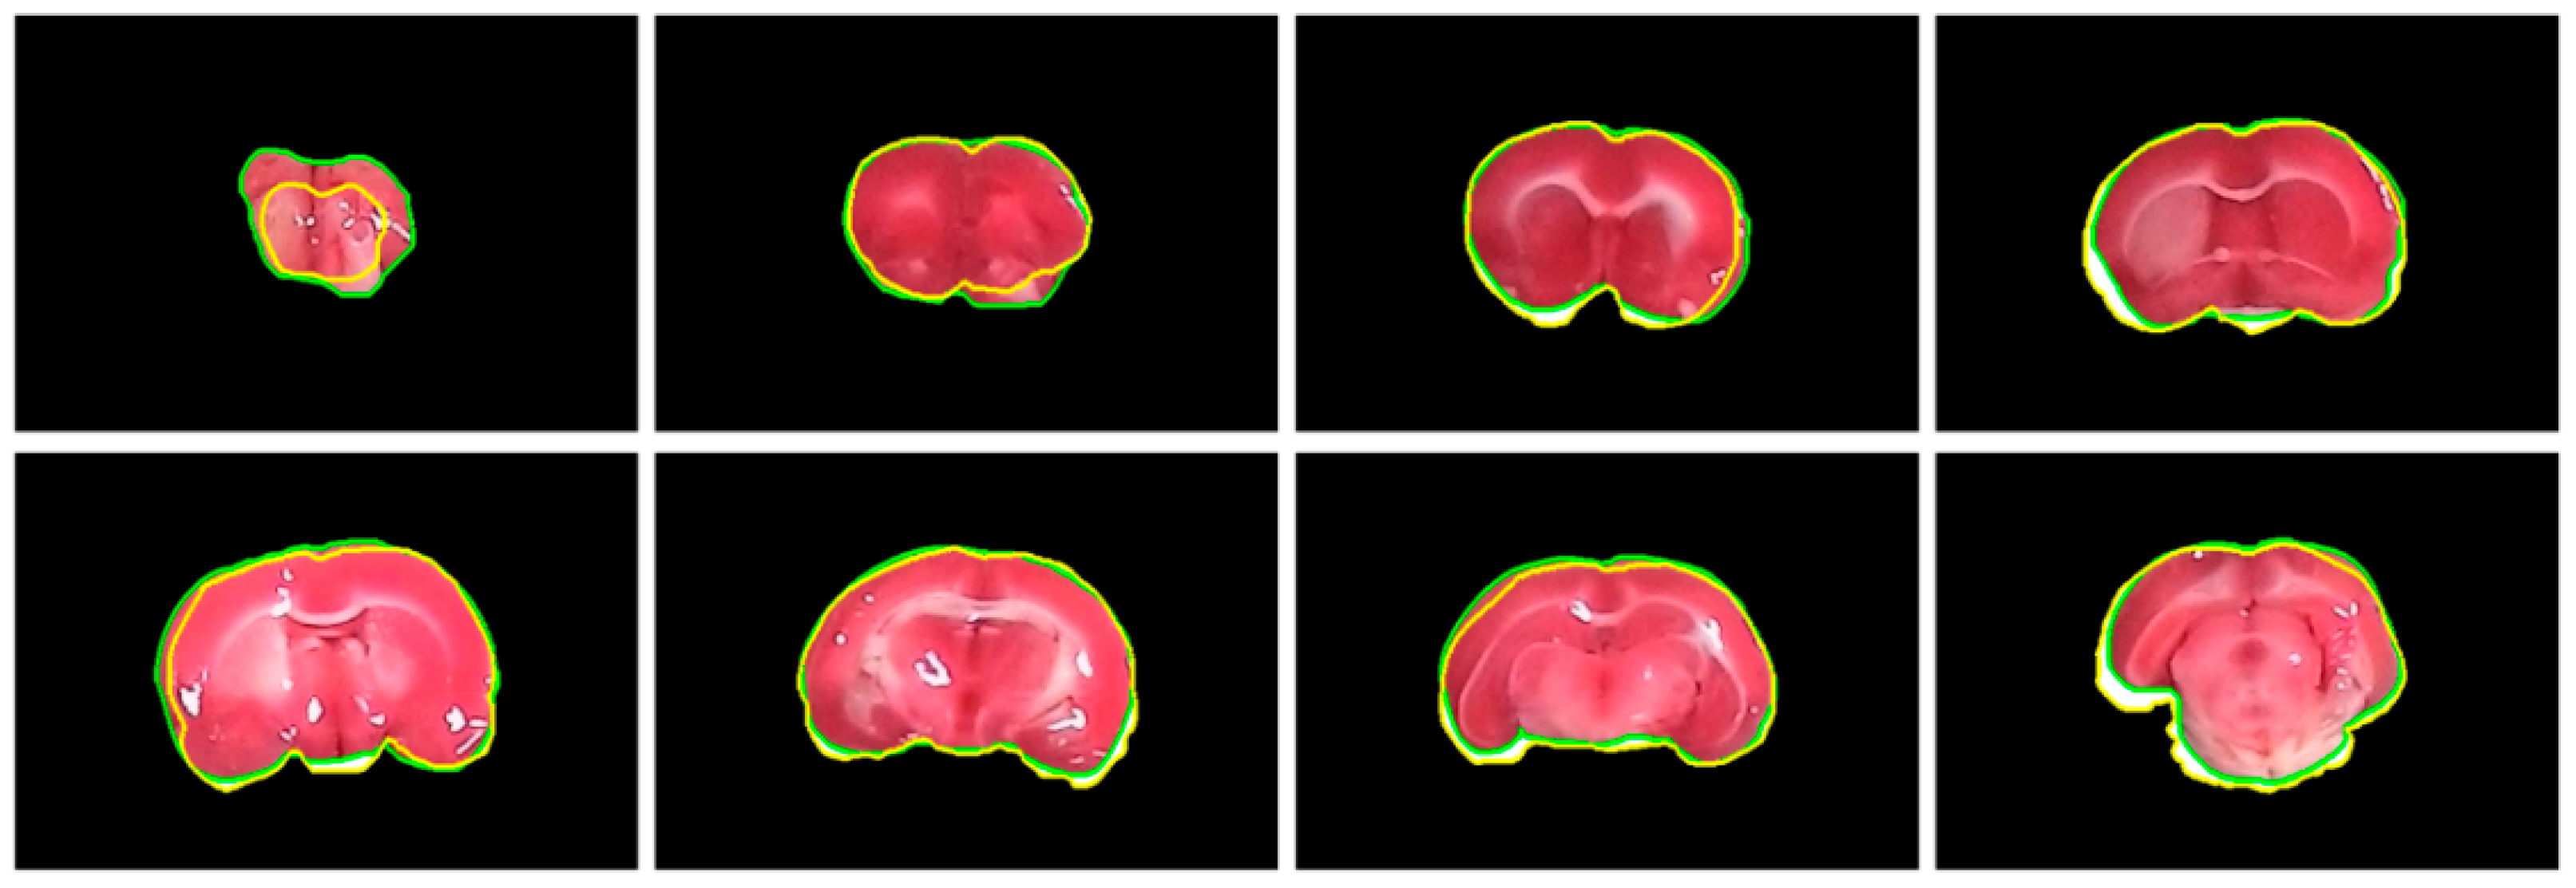

4.3. Evaluation of Rat Brain Extraction